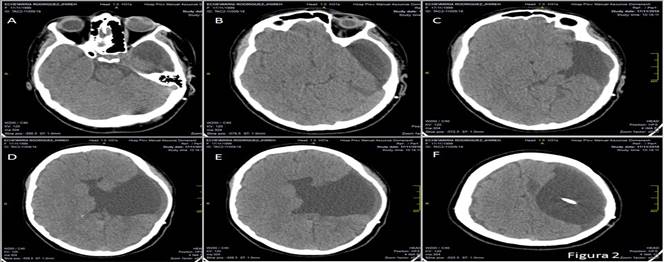

Se practicó de urgencia, una derivación ventricular izquierda al exterior con el objetivo diagnóstico y terapéutico de aliviar la hipertensión del líquido cefalorraquídeo y monitorizar la presión intracraneal, que se mantuvo en valores entre los 250 y 300 mm de H2O. El estudio evolutivo por TAC evidenció el agujero de trépano frontal izquierdo con catéter de derivación y las estructuras de línea media estaban desplazadas menos de 5 mm. Al examen físico, la paciente recobra su nivel de consciencia y se toma la decisión de colocar un sistema derivativo ventrículo peritoneal. La cirugía no mostró complicaciones y la paciente se restableció. Fue egresada del hospital con completa recuperación neurológica de la consciencia, el defecto motor de iguales características y sin convulsiones sobreañadidas (Figura 2).